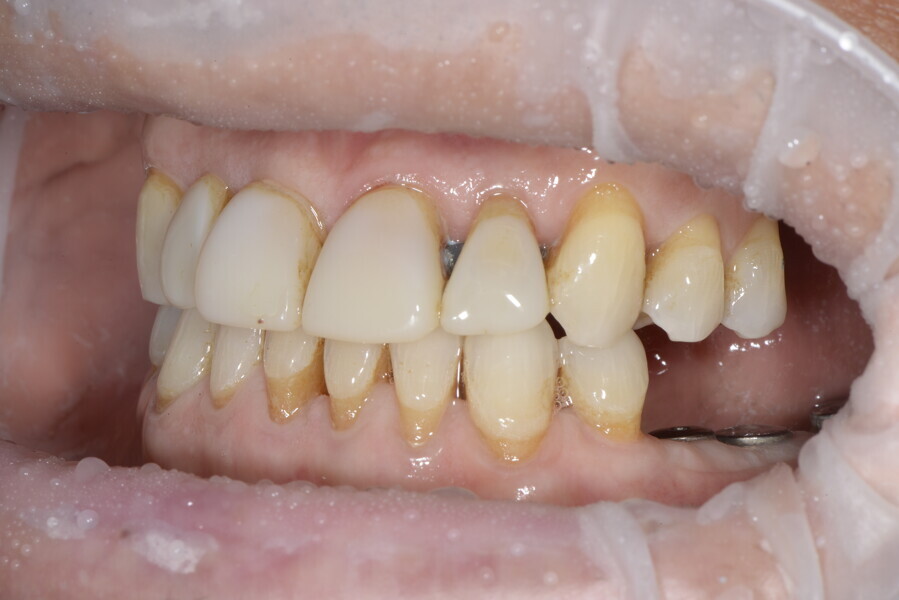

This patient, like all patients requiring interdisciplinary rehabilitation, had to first undergo periodontal treatment and caries restoration (Fig. 17). At the same time, it was important to rehabilitate swallowing with Froggymouth and relax the masticatory muscles and relieve the TMJs with an occlusal device. We could then study the orthodontic treatment plan using Invisalign ClinCheck (Align Technology) and showed the treatment plan to the interdisciplinary team and to the patient (Fig. 18). We were then able to create the correct sequence of orthodontic treatment, bone augmentation and implant surgery needed for the posterior edentulous spaces.

After the first phase of aligner treatment, we had achieved better inter-arch coherence, better maxillary arch expansion, and some space for improving the anterior tooth proportions restoratively (Fig. 19). We then temporarily restored the anterior teeth directly with composite, closing the spaces, improving the tooth proportions and further increasing the maxillary arch expansion (Fig. 20). We used restorative arch expansion to reduce the orthodontic destabilisation of the teeth to achieve the correct inter-arch coherence and retain the teeth in the cortical bone.38 A refinement aligner phase was undertaken to improve the final alignment of the gingival zenith and to improve the inter-arch coherence (Fig. 21). The periods of the first orthodontic phase and of the refinement were used to augment the mandibular and maxillary bone and to place the implants (Fig. 22). At the end of the orthodontic treatment, the case was finalised with ceramic veneers in the anterior area and temporary restorations on the implants in the posterior area (Figs. 23–26).